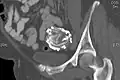

Lithopedion aangetroffen aan de buitenzijde van de blaas, nabij de baarmoederhals. -